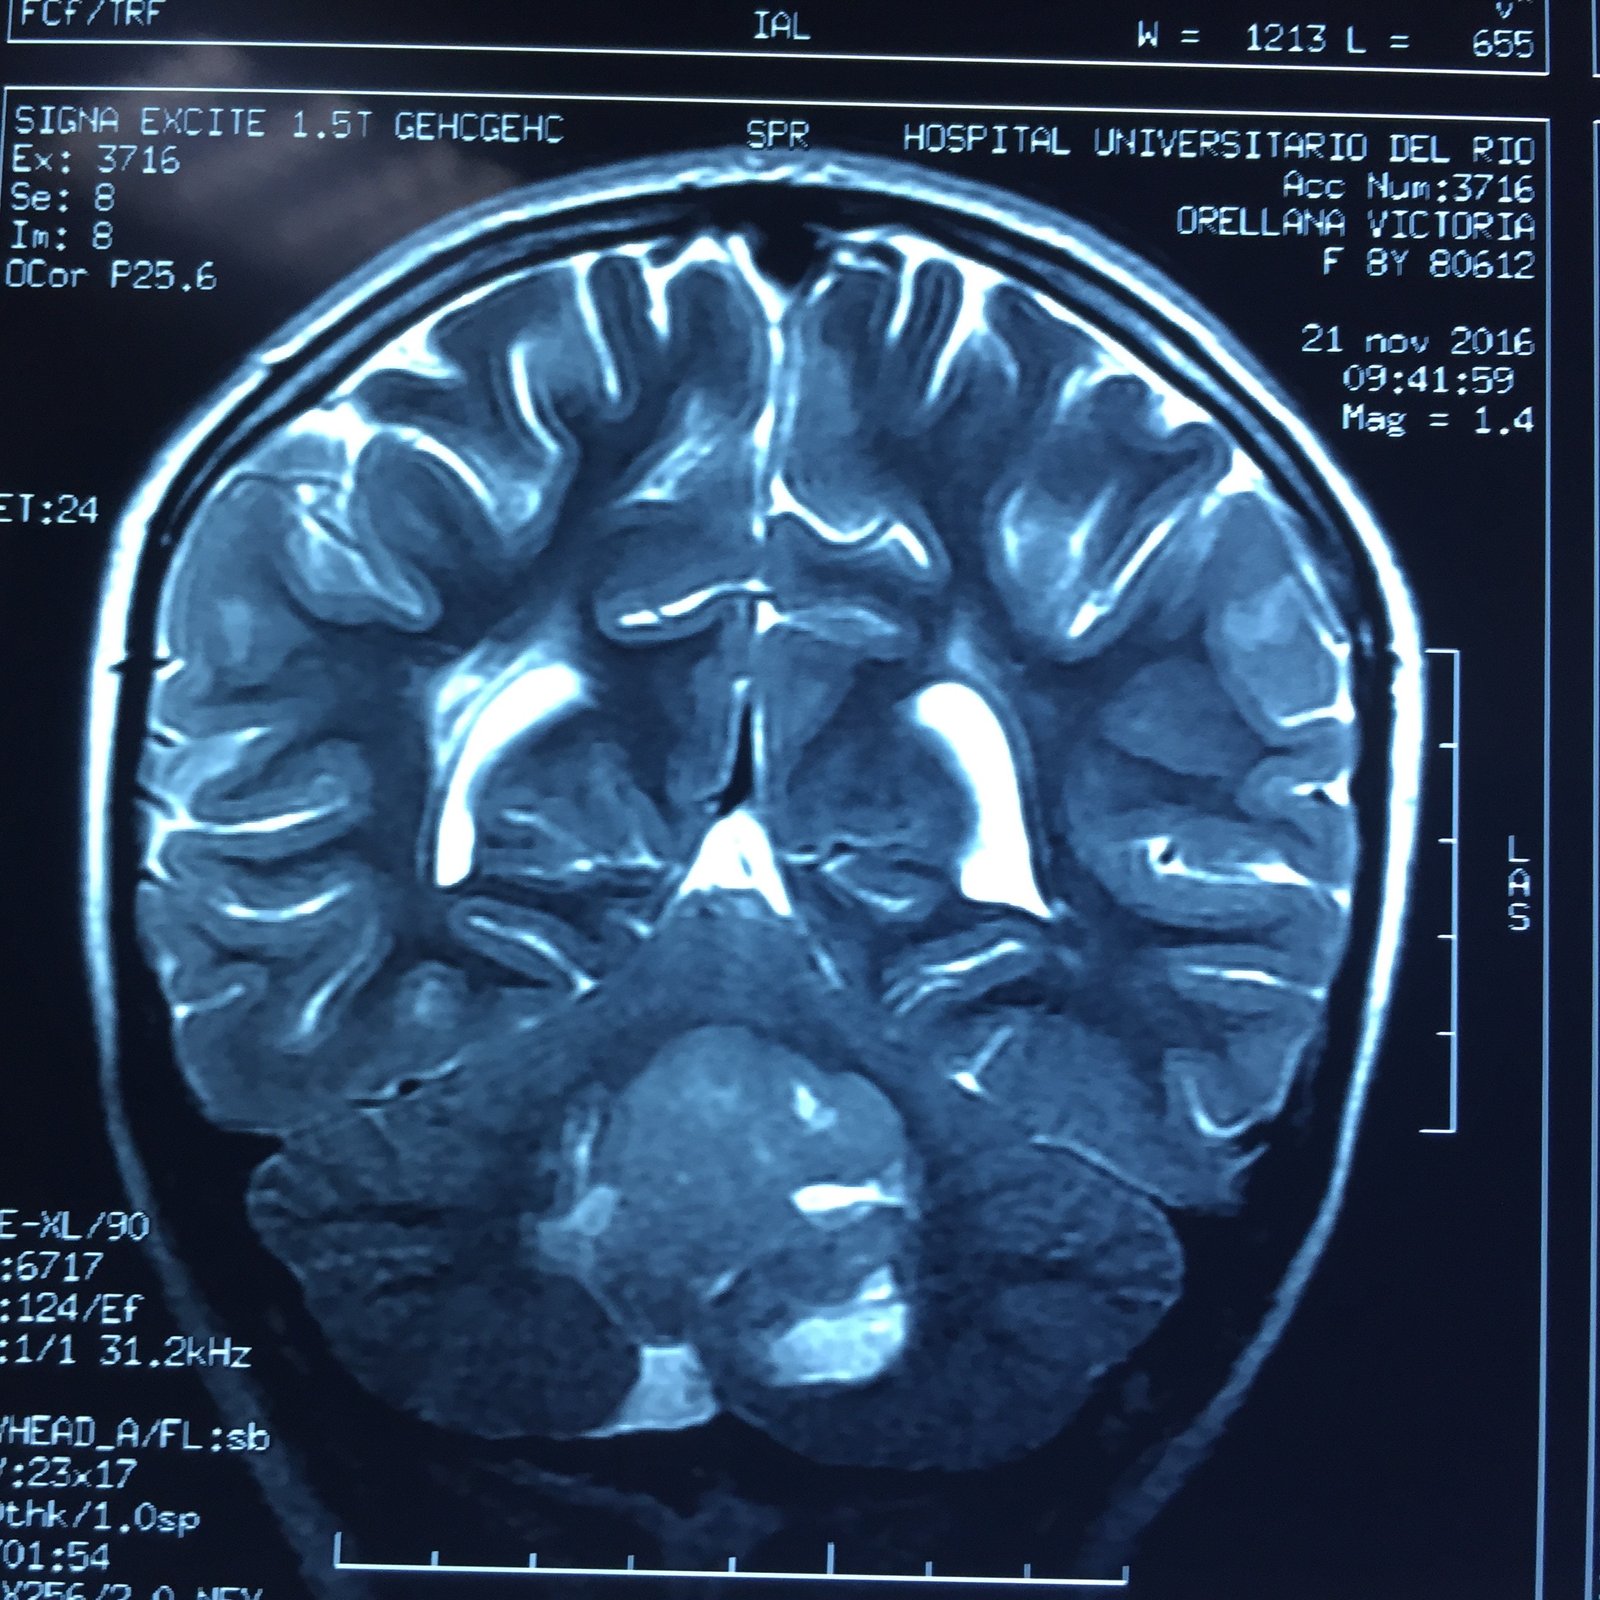

MEDULOBLASTOMA

DESCRIPCIÓN